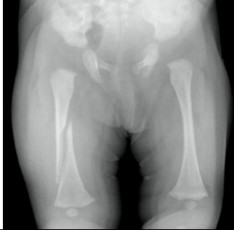

You are seeing a 10-month-old in your office for the first time for a well child check. The child was born by C-section for breech presentation without complication and has had no hospitalizations or surgery. She has had three sets of immunizations. Her exam is unremarkable except for uneven height of her knees (positive Galeazzi sign) and limited abduction of the right leg.

What is the most likely diagnosis?

Developmental Dysplasia of the HipWhat is the best means to make the diagnosis? (Hint: looks at the child’s age)

Hip x-ray over 6 mos of age. (if the child is less than 4 mo, then US is the test of choice) -

A 6-week-old infant is brought to your clinic with a swollen left thigh. The baby has been irritable for the last two days especially with diaper changes. You obtain the following radiograph. After gathering a history from the caretakers, there is no known mechanism to explain the injury.

What other radiographic studies are recommended in this context to screen for occult injuries (be specific)?

Skeletal Survey and Head CTIn addition to medical therapy, what else needs to be done at this point?

Notify social work, CPS (DCS), and law enforcement. Call CPS must be included to get credit. -